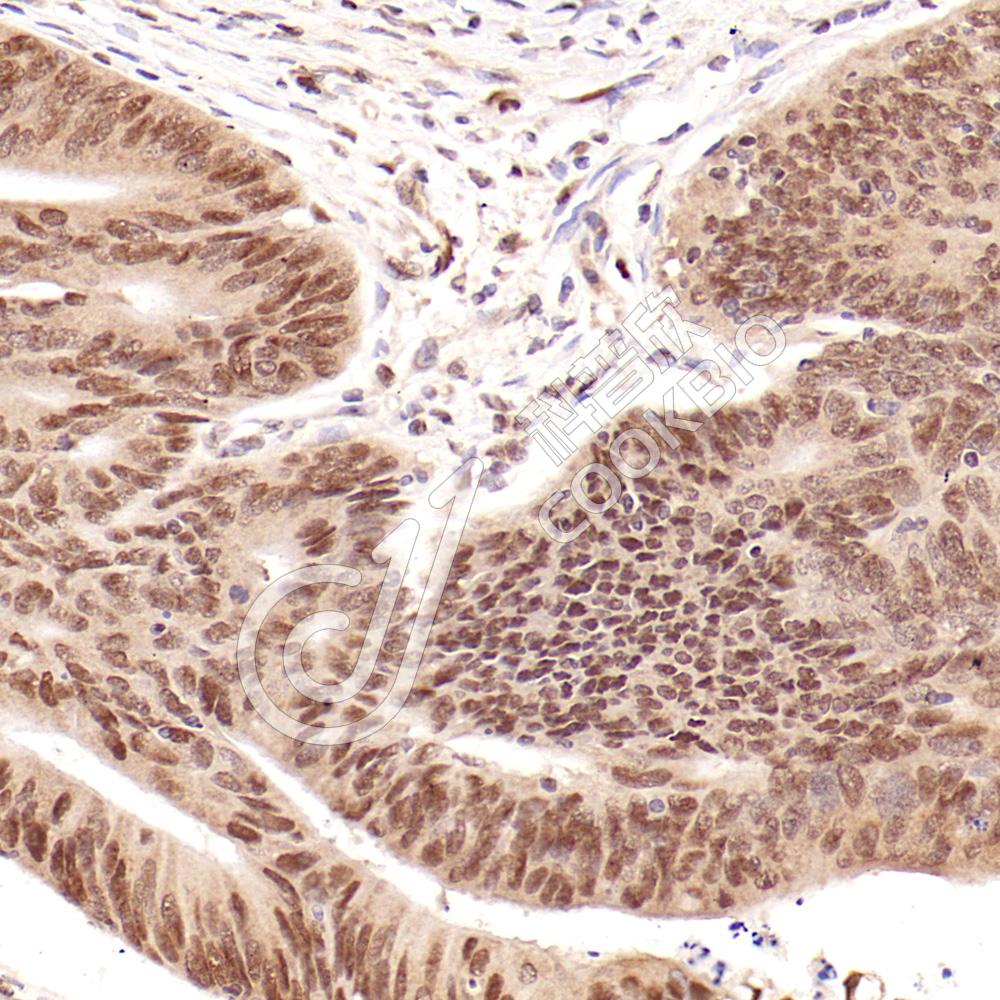

IHC检测Notch2蛋白(货号 K1341931).

样品: 人结肠癌, 4%多聚甲醛 (货号KSG1101) 固定12-24小时.

抗原修复: 柠檬酸抗原修复液(干粉, pH 6.0) (KSG1201), 98℃, 20分钟.

—抗: 1: 900稀释, 4℃ 孵育过夜.

二抗: S-vision免疫组化多聚二抗(山羊抗兔),即用型 (货号KB3906), 室温孵育20分钟.